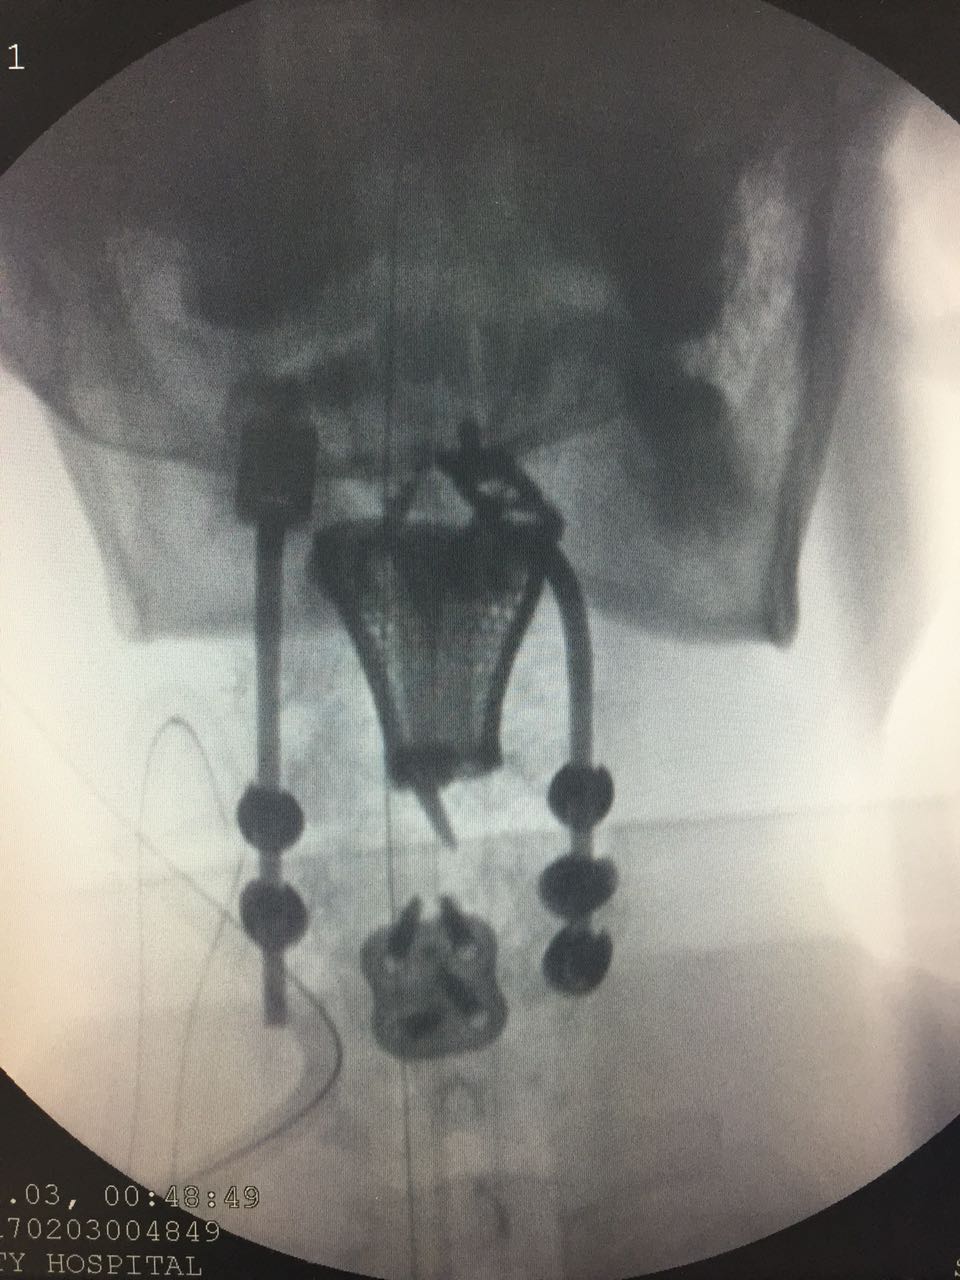

Photo of 3d printed spine of the patient . This was used to measure the gaps between the vertebrae to ensure that the final replacement vertebrae would fit in perfectly. Photo of 3d printed spine of the patient . This was used to measure the gaps between the vertebrae to ensure that the final replacement vertebrae would fit in perfectly.

A team of surgeons at Medanta – The Medcity in Gurgaon, India, managed to get 3d print titanium replacements of her damaged first, second and third vertebrae and insert them in her spine in a 10 hour surgery. CT and MRI scans of the spine were obtained first, which were then studied to ensure that the final, 3d printed vertebrae would fit in perfectly. The 3D printed titanium replacements were also tested for biomechanics and stress risers, and multiple design teams from India, US and Sweden provided the final version of the implants to the hospital where the surgery was performed.